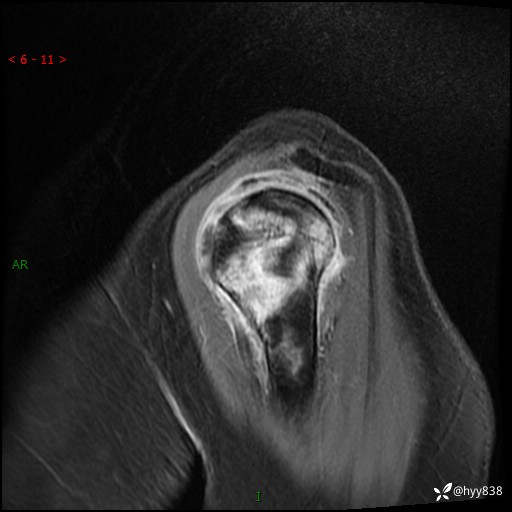

肱骨正侧位片

肱骨MRI平扫(axi T1WI+cor T2WI-fs)+CE-fs(COR+SAG)